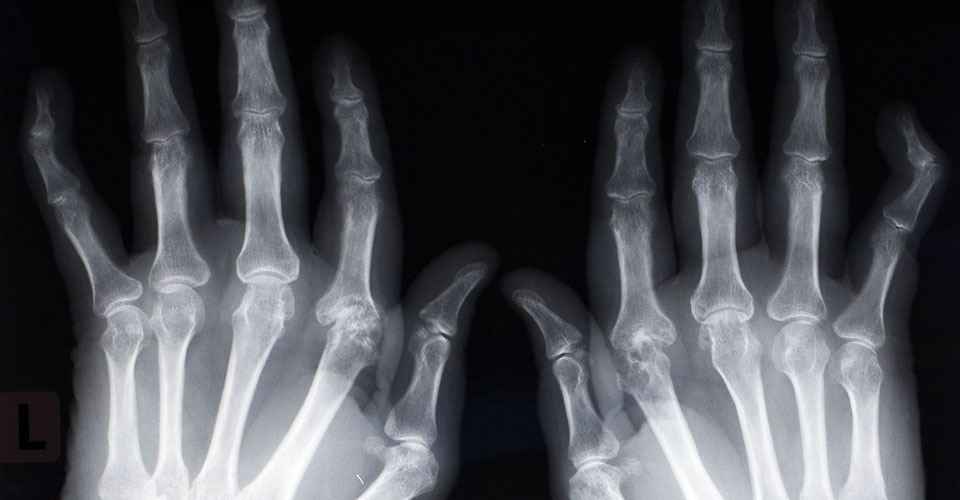

RA usually affects the smaller joints of the hands and feet, but can also affect larger joints such as the hips and knees. As well as the musculoskeletal system, RA can affect body systems and organs such as the lungs, heart, and eyes. Organ changes are most often the result of vasculitis and manifest as ischaemic changes.

Below you will see a range of joint erosion examples.

- Symptoms predominantly presenting in the small joints in hands and feet, plus or minus larger joints.

- Signs predominantly presenting in small joints in hands and feet plus or minus larger joints.

- Functional impairment in hands and feet (fine and gross motor skills).

- Joint deformity (postural, subluxation, dislocation).

- Joint degeneration - joint erosion may only be identifiable on MRI or CT.